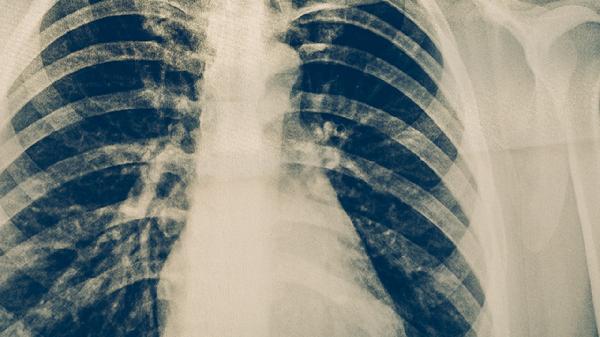

肺结核的预防需要采取综合措施。与肺结核患者密切接触者应定期进行结核菌素试验或胸部X线检查。保持良好生活习惯,增强免疫力有助于预防感染。出现咳嗽、咳痰、低热、盗汗等症状时应及时就医检查。确诊肺结核后要规范治疗,按时服药,避免中断治疗导致耐药性产生。患者咳嗽时应掩住口鼻,痰液要消毒处理,生活用品要单独使用并定期消毒。